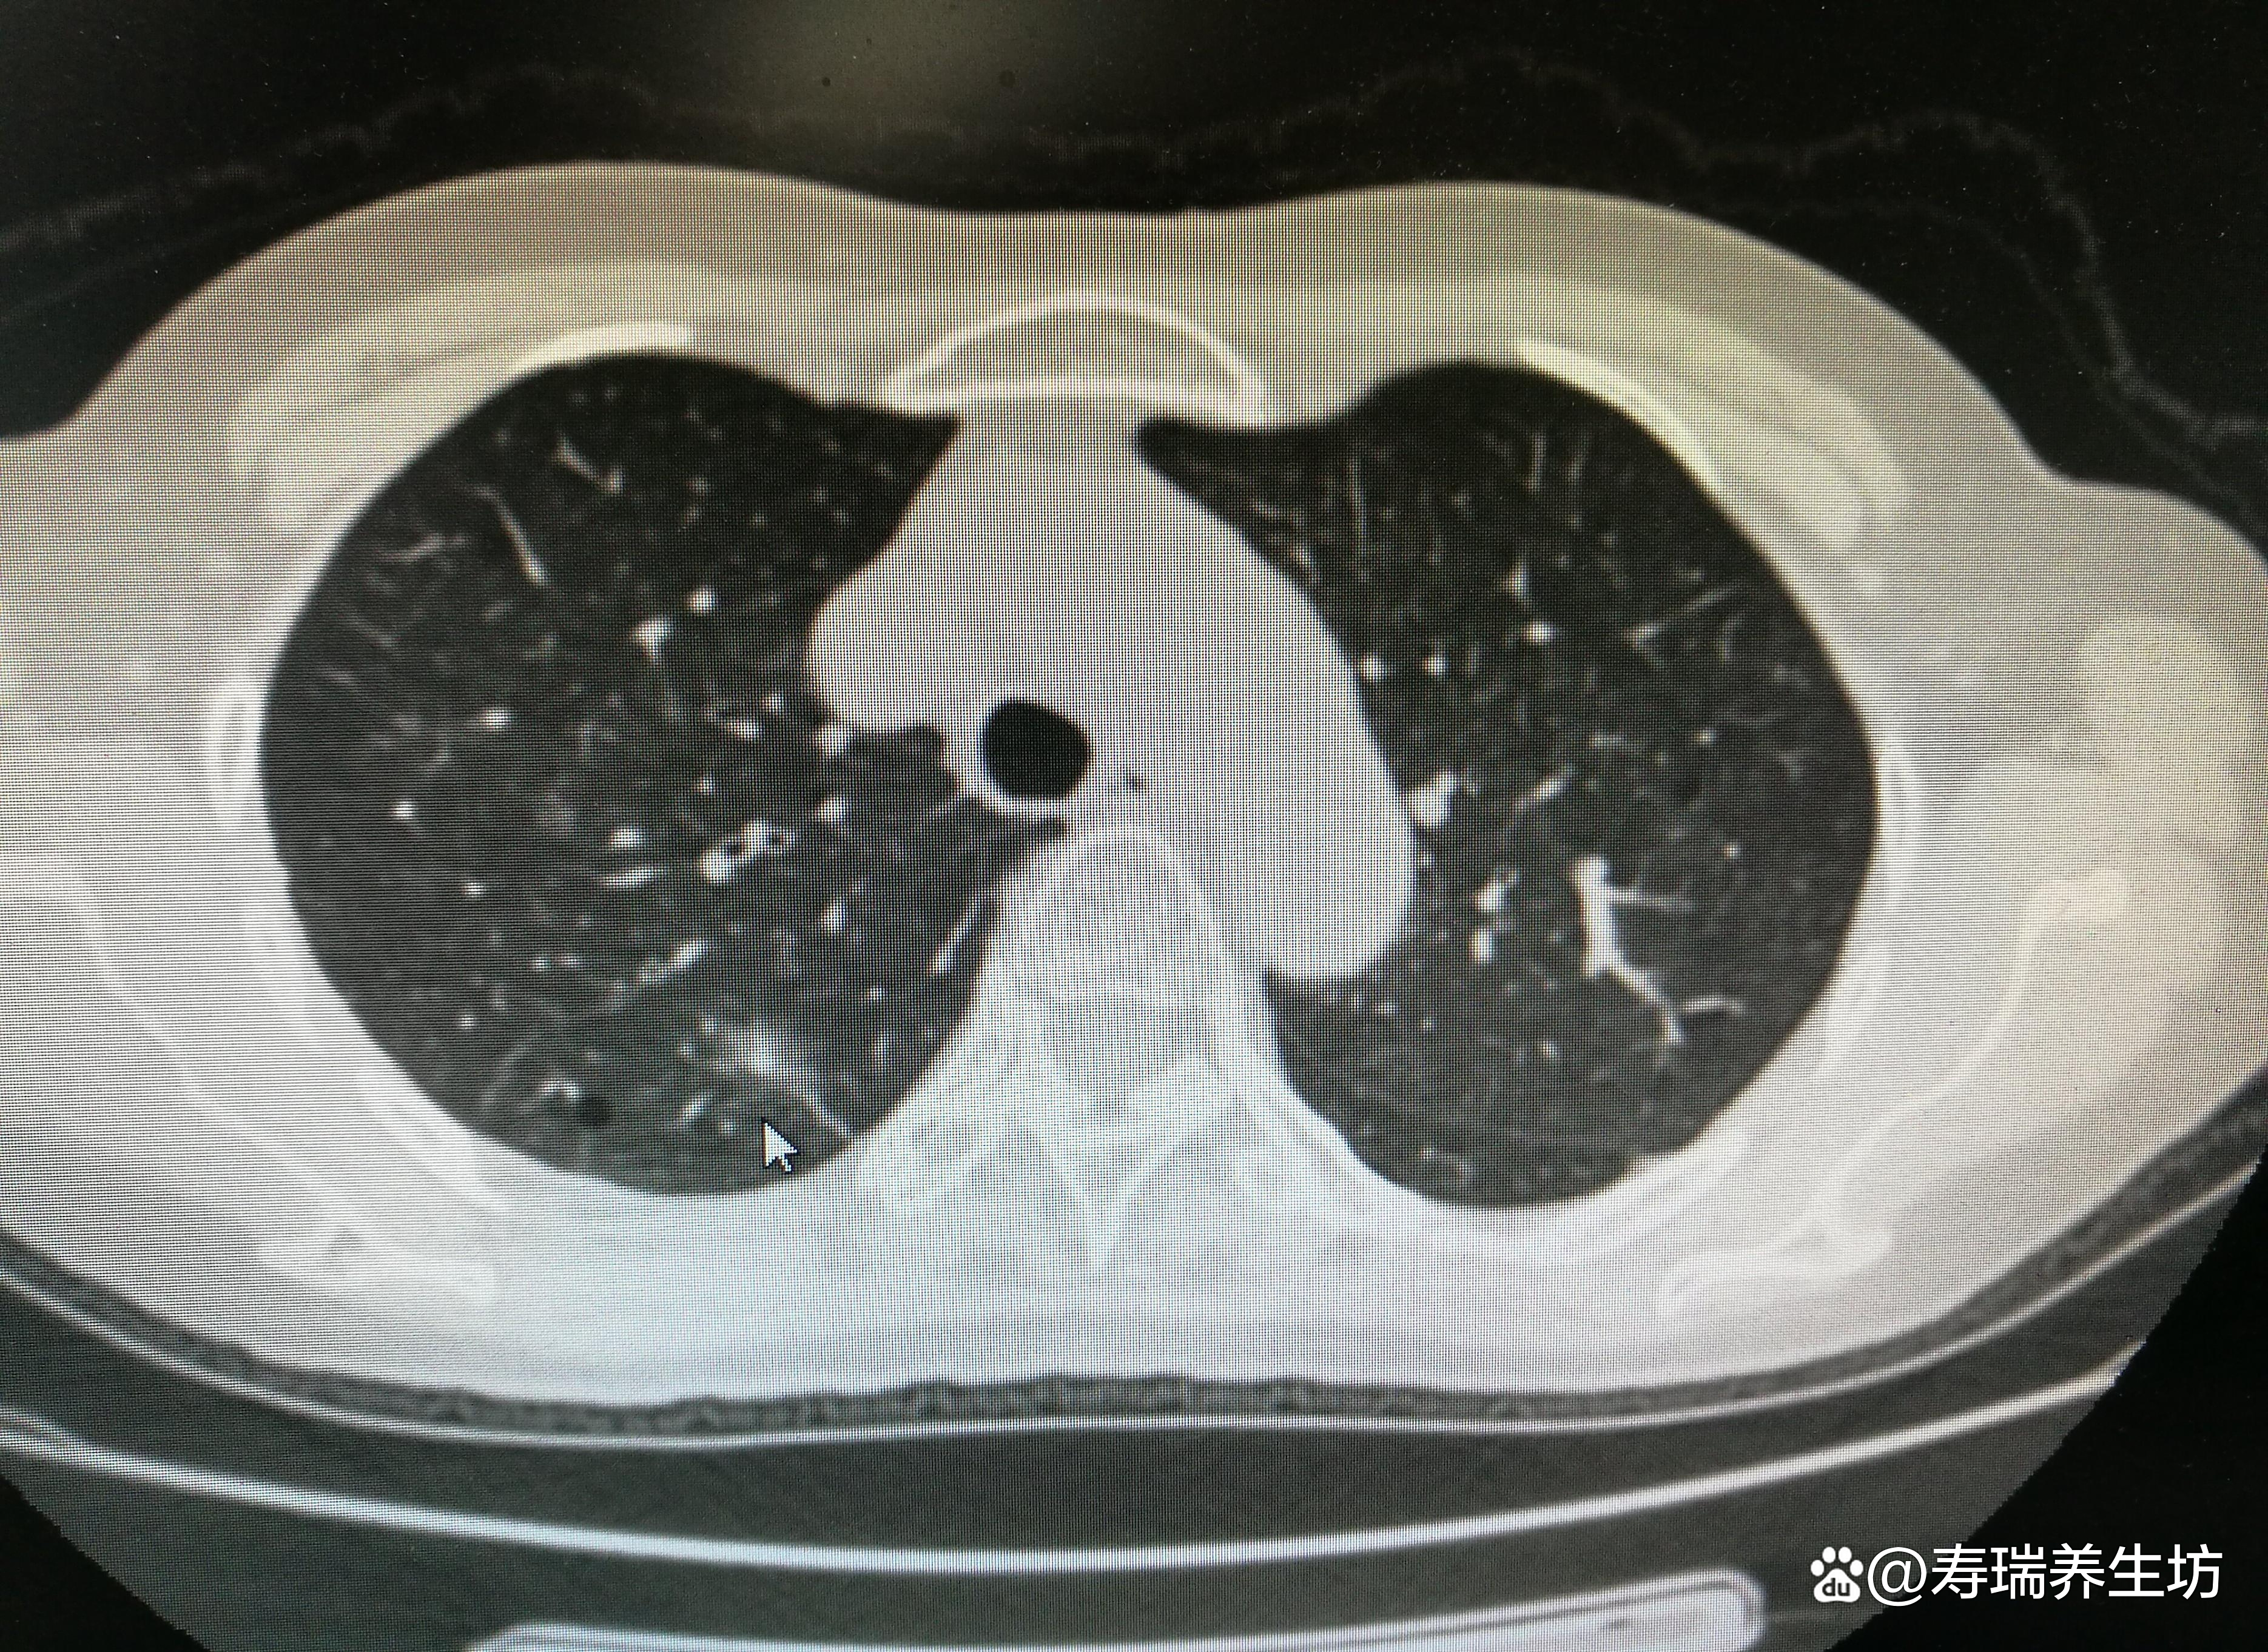

4、6mm肺部结节一年后没了是正常的以下是具体分析1 肺部结节的定义肺部结节是指在胸片或CT影像中呈现的高密度阴影,其直径通常小于30mm6mm的肺结节属于小结节范畴2 结节消失的可能性6mm的肺结节一年后消失是完全可能的因为肺结节中,良性的占绝大部分其中很多结节是由炎性感染引起的,在。

12、从病因看,6mm肺结节的成因主要包括三类感染性疾病如肺炎肺结核等,炎症消退后可能遗留结节,属于炎症修复后的瘢痕性改变良性肿瘤如错构瘤硬化性血管瘤等,这类结节生长缓慢,通常无侵袭性恶性肿瘤包括原发性肺癌或转移性肿瘤,需通过病理检查确认从严重性看,6mm肺结节多数为良性,尤其。